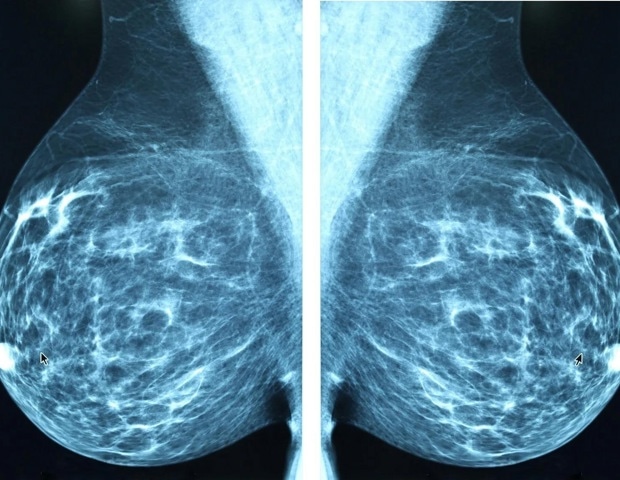

Αύξηση των κρουσμάτων καρκίνου μαστού

Η συχνότητα εμφάνισης καρκίνου μαστού σε γυναίκες ηλικίας 15 έως 39 ετών έχει αυξηθεί κατά μέσο όρο 0,6% ετησίως από το 1975 έως το 2022. “Οι νεαρές γυναίκες με καρκίνο του μαστού είναι πιο πιθανό να υποφέρουν ψυχολογικά και σωματικά μετά τη διάγνωση σε σύγκριση με τις μεγαλύτερες ηλικίες,” δήλωσε η Δρ. Άν Χ. Πάρτριτζ, αναπληρώτρια διευθύντρια της ιατρικής ογκολογίας και επικεφαλής στρατηγικής κλινικής στο Ινστιτούτο Καρκίνου Dana-Farber.